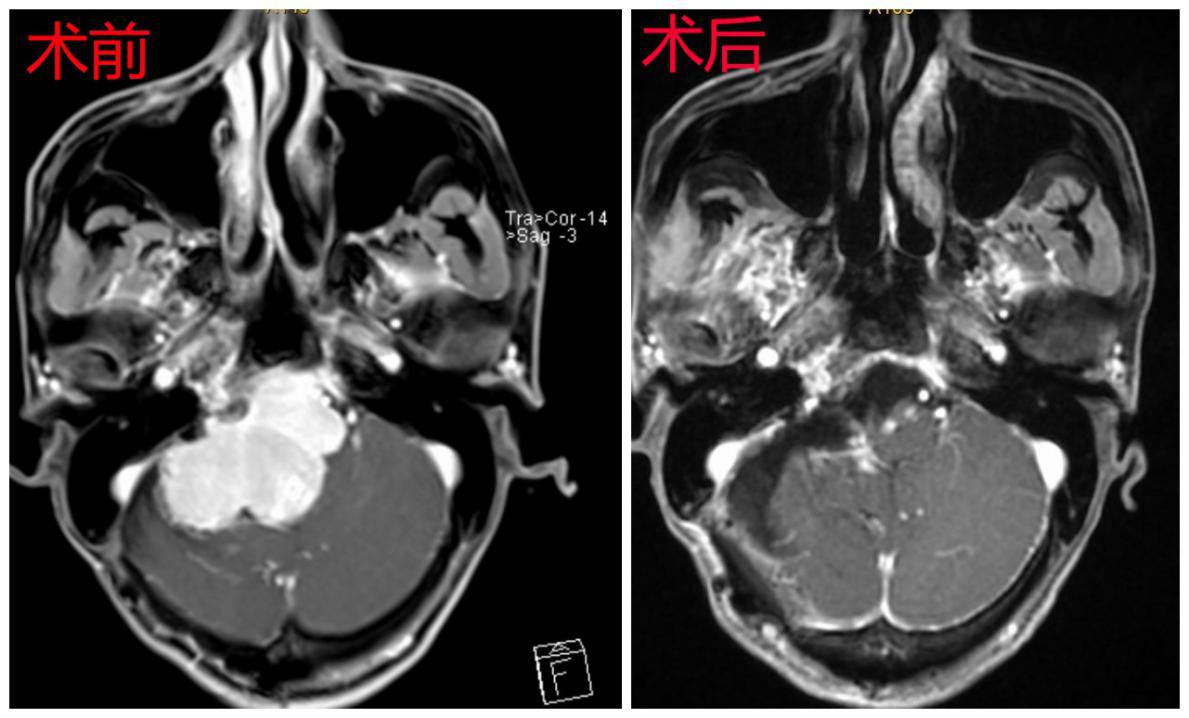

术前术后对比图

在尚未联系深圳市第二人民医院之前,曾先生病情急转直下,突然出现急性脑积水、高颅压、脑疝昏迷等症状,2018-04-01在当地医院急诊行“脑室外引流术”,然而这仅是权宜之计。曾先生家属根据北京天坛医院专家意见联系深圳市第二人民医院脑科中心医师后于2018-04-03转入我院,由神经肿瘤病区颅底组接收了曾先生。深圳市第二人民医院脑科中心主任、颅底肿瘤协作组组长蒋太鹏教授组织颅底组成员王建中副主任医师、林恒州副主任医师、左大辉主治医师、刘晓佳主治医师对曾先生病情进行全面评估发现,曾先生的复发肿瘤病理为“恶性孤立性纤维性肿瘤”,肿瘤目前已侵占右侧枕骨大孔区、桥小脑角区、斜坡、天幕及鞍上等部位,病变范围广泛,该肿瘤供血极其丰富。

因肿瘤生长区域有众多重要血管及颅神经通过,还压迫生命中枢脑干,解剖结构复杂,且既往有手术病史,肿瘤粘连严重,可能包绕各颅神经和重要血管,手术难度极大,术中极易损伤重要颅神经及血管,而且一次性完全切除肿瘤极其困难,术后也极易出现呼吸障碍、面瘫、吞咽障碍、昏迷、四肢瘫痪等严重并发症。对于医生来说这是一个非常棘手的病例,施行手术是一个极大的挑战。考虑到患者已辗转国内外多家医院均未得到有效救治,放弃手术即等于放弃生命,通过详细告知家属病情,家属表示积极配合治疗,在此基础上神经外科全体医师进行再次讨论,得到了神经外科首席专家高永中教授和全体医师的支持,并制定了详细的手术治疗方案及应急预案。

考虑到曾先生的脑室外引流管已留置3天,未来的3天为清明小长假,若等节后手术会增加颅内感染风险。随即蒋太鹏教授将患者病情通报手术室钮敏红、龚喜雪两位护士长及麻醉科杨新平副主任,她们表示全力配合为患者进行手术。时间就是生命,2018.04.05清明节放假第一天全体医护人员放弃休息,为曾先生施行手术。术中肿瘤供血极其丰富,在分离三叉神经和迷走神经周围肿瘤时曾出现“脑心反射”致患者心跳骤停,幸好丰富经验的手术团队及时处理,手术得以继续进行,历时约12小时,是一场不折不扣的拉锯战,对医师的精力、体力有极大的要求,手术顺利将肿瘤近全切除,将患者生命从死神的手中重新夺回。